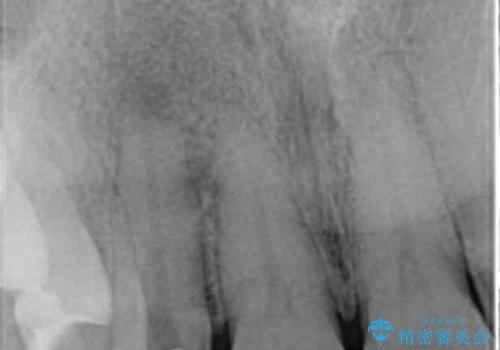

- 前歯の付近、歯ぐきを押すと違和感を感じその改善を求めて来院されました。

X線検査の結果、失活(感染根管)であることが判明したので、感染根管治療後セラミック補綴を計画します。